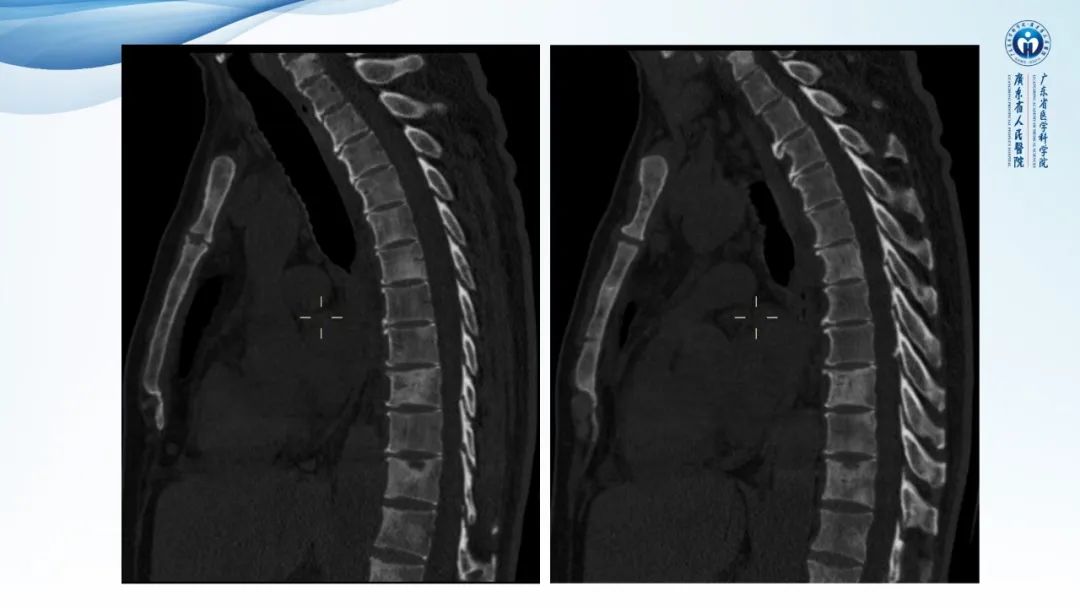

一例表现为弥漫中轴骨骨质增生硬化病变讨论

• 中轴骨多发成骨为主病灶-POEMS综合征/硬化性骨髓瘤

• 慢性骨髓炎(非结核分支杆菌)、SAPHO综合征 待排除